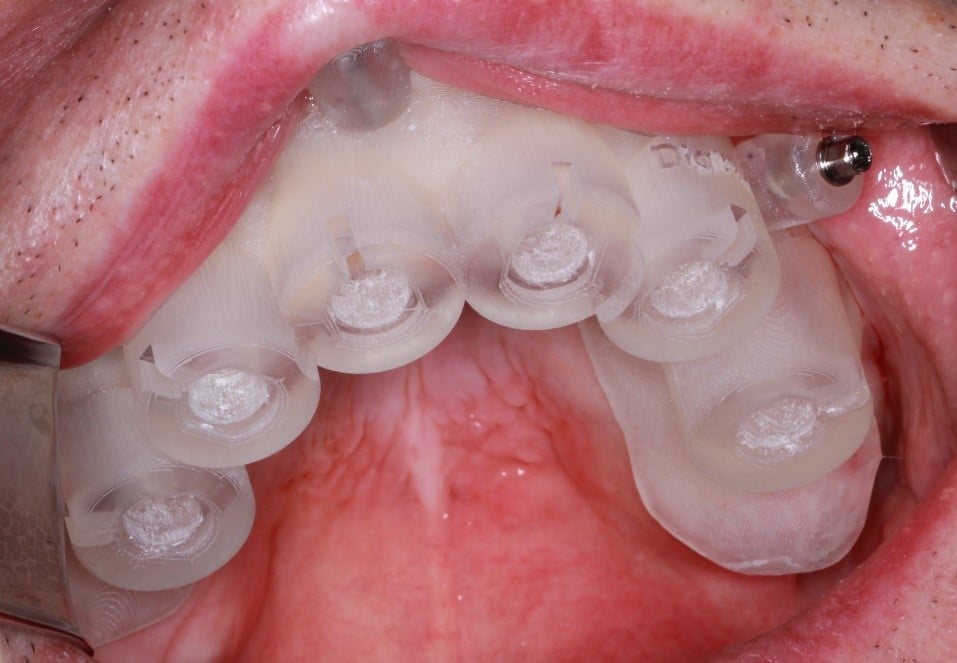

Odată planficată și agreată poziția și axul de inserție al fiecarui implant, tehnicianul DigiRay efectuează designul șablonului chirurgical și printarea acestuia dintr-o rășină bio-compatibilă.

Pentru a asigura stabilitatea ghidului chirurgical pe câmpul protetic, șablonul chirurgical a fostfixat cu ajutorul celor 3 pini de stabilizare plasați în zona posterioară și în zona frontală.